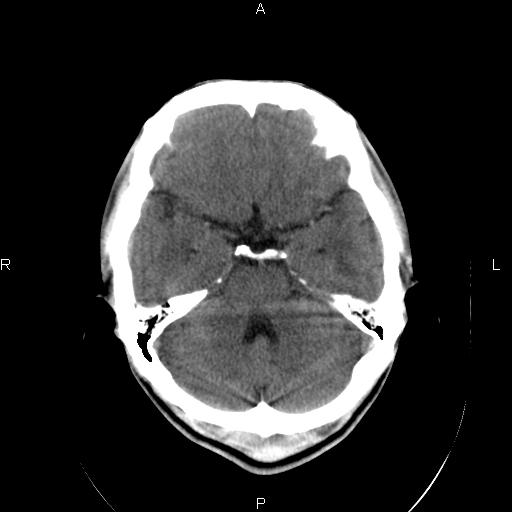

男性,40岁,反复头痛,视物旋转一月余,无呕吐,pe未见明确异常。

我的问题是上矢状窦高密度怎么解释?请各位专家不吝指教,谢谢!

可结合增强或mrv检查除外上矢状窦血栓。

未见明显异常,必要时mri

颅脑平扫未见异常,必要时mri检查。

颅脑ct轴位平扫颅内未见明确异常;建议必要时行mri检查。